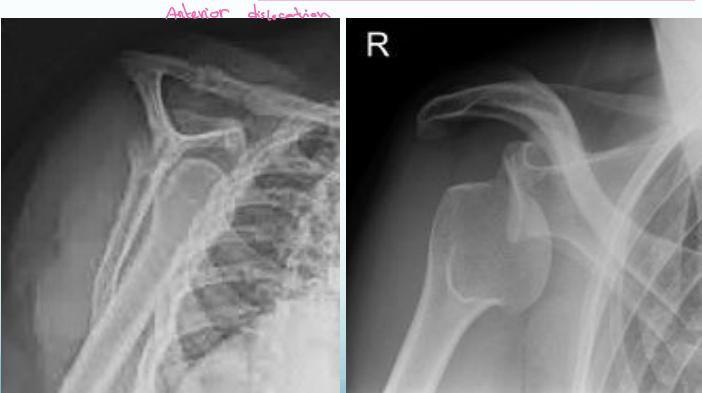

Anterior Shoulder Dislocation

Definition: The humeral head lies anterior to the glenoid

X-rays:

- AP (& lateral scapular) views

- Overlapping shadows of humeral head and glenoid

- Humeral head lies below and medial to glenoid

Important: Rule-out greater tuberosity fracture